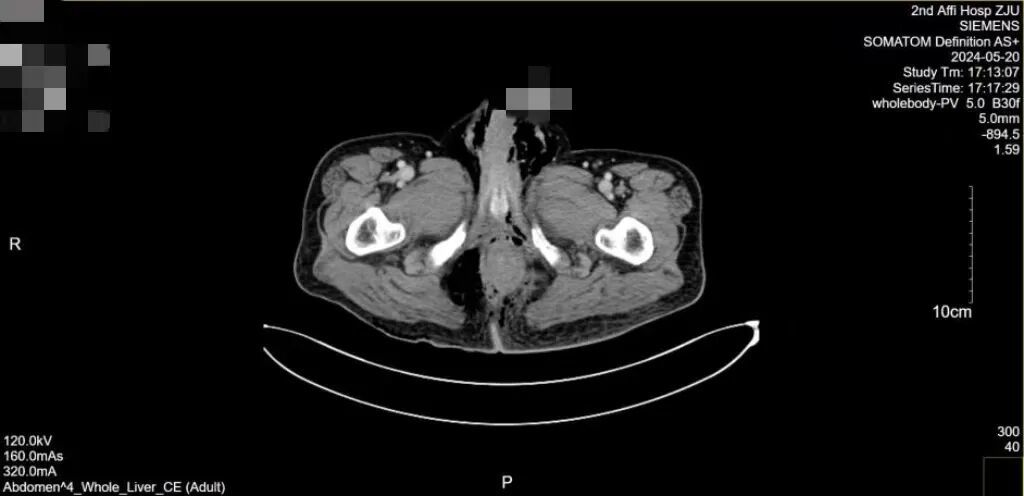

当来到浙江大学医学院附属第二医院急诊时,患者的情况已经相当复杂:全腹 CT 增强扫描提示直肠左侧壁不连续,周围渗出、积液积气,直肠周围筋膜增厚,盆底周围、会阴渗出、积气,两侧腹股沟区、盆壁、左侧腹腔多发积气。

患者腹部 CT 增强扫描报告